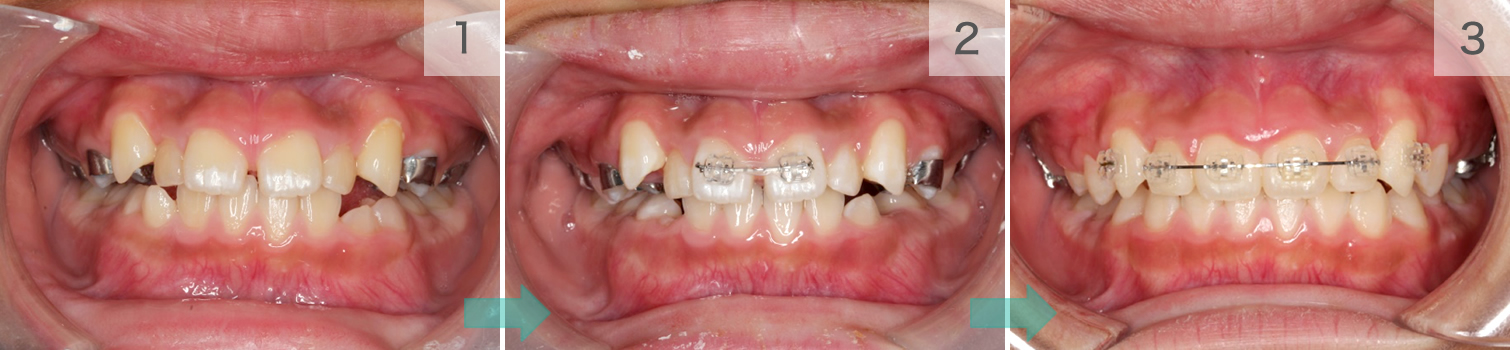

症例01. Sectional

混合歯列期や限局矯正に、ブラケットとワイヤーを用いて

並べます。凸凹だけでなく、噛み合わせの深さなども変え

られます。

| 治療内容 | 1:すきっ歯と八重歯が気になる 2:まず前歯を閉じる 3:スペースを使ってきれいに並べる |

|---|---|

| 期間 | 半年~1年 |

| 費用 | 300,000円+税 |

| リスク | 歯の動きに伴ったむずがゆさや軽度の痛みが出る可能性があります。 数日程度で慣れてしまいます。 |